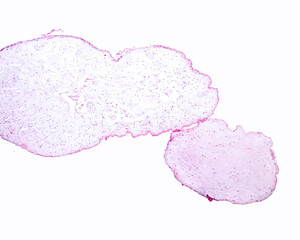

Hydatidiform mole..

Hydatidiform mole